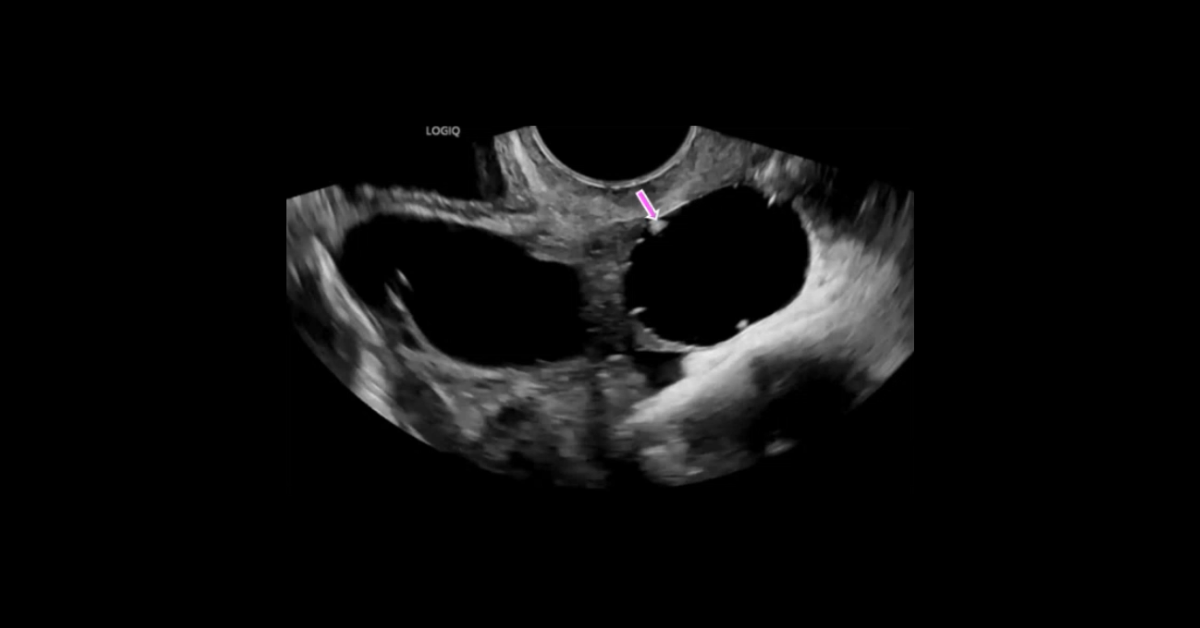

Presented by Vincent Mellnick, MD at Practical Radiology 2025. The upper gastrointestinal tract can be oft-overlooked site of disease in the emergency department patient, but is frequently be the site of pathology, including inflammation/infection, ischemia, obstruction, perforation, and hemorrhage. This talk will discuss common (and some uncommon) conditions causing these presentations in the esophagus, stomach, and duodenum, with emphasis on CT findings.